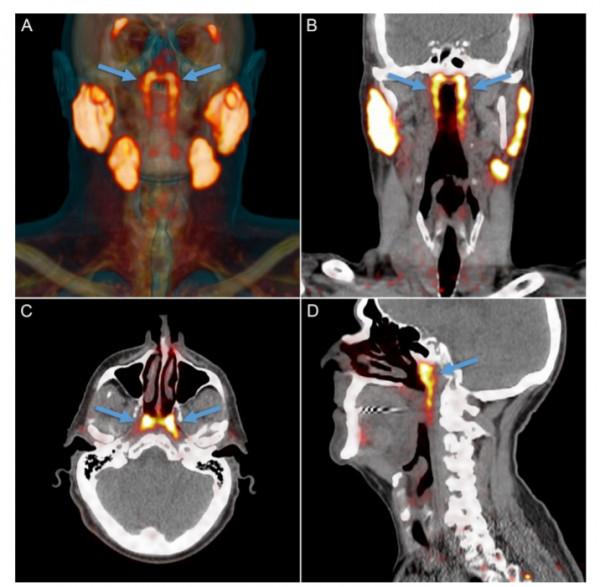

在以往的醫學記載中,人類只有三個明顯的唾液腺——舌下腺、頜下腺和腮腺,分別位於舌頭下方、下頜下方和臉頰後部的下頜背面。除此之外,咽喉和口腔粘膜組織中或許也散佈著上千個極小的唾液腺。它們分泌唾液,幫助我們咀嚼、吞嚥和消化食物,並保持我們的口腔溼潤及牙齒健康。而這次新發現的隆凸唾液腺位於鼻子後面一塊被稱為咽鼓管隆凸的軟骨上,平均長度約1.5英寸(即3.9釐米)。

Wouter Vogel是在探查頭部、頸部或腦部癌症放療後的唾液腺損傷(導致消化、語言和口腔感染增加等問題)時,發現這組從未被描述和記錄過的頸部唾液腺的。為了證實人體的隆凸唾液腺這一最新發現的非偶然性。Vogel及其同事對100名患者進行了掃描(由於研究者是聚焦前列腺癌,所以其中99位患者為男性),還解剖了兩具屍體,最終發現所有人都擁有這一“新的”腺體。這一驚喜發現於10月16日正式釋出在《放射治療與腫瘤學》(Radiotherapy & Oncology)上。